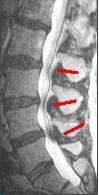

MRI

The MRI has become the most frequently used study to diagnose spinal stenosis. The MRI uses electromagnetic signals to produce images of the spine. MRIs are helpful because they show more structures, including nerves, muscles, and ligaments, than seen on x-rays or CT scans. MRIs are helpful at showing exactly what is causing spinal nerve compression.[15]

The diagnosis of spinal stenosis involves a complete evaluation of the spine. The process usually begins with a medical history and physical examination. X-ray and MRI scans are typically used to determine the extent and location of the nerve compression.